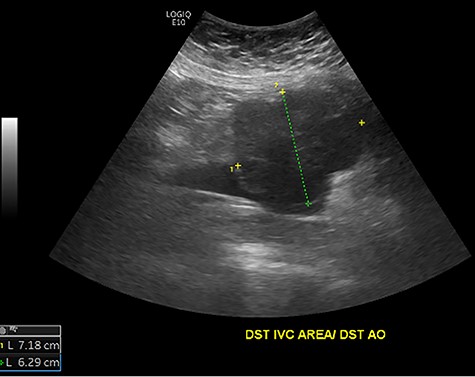

Initial ultrasound showing a large heterogenous, hypoechoic mass like lesion overlying the IVC.

The patient had a body mass index of 40, so combined with her presentation, age and gender. The presumptive diagnosis was of gallbladder pathology, which prompted an abdominal ultrasound. Ultrasound revealed a large 7.7 × 6.3 × 7.2 cm heterogenous, hypoechoic masslike lesion overlying the IVC (Fig 1). Abdominal CT was performed, which revealed an 8.9 × 7.9 × 9 cm multilobulated, heterogeneous soft tissue mass in the right hemiabdomen, encasing the IVC and partially encasing the distal abdominal aorta (Figs. 2–4). CT-guided biopsy was performed, which revealed an LMS.